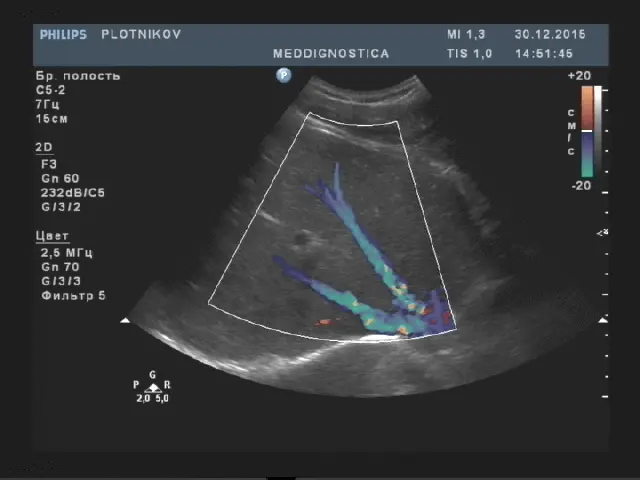

Товщина правої частки до 12.5см, товщина лівої частки до 6 см, товщина хвостатої частки до 3 см. Край лівої частки гострий. Поверхня гладка, ехогенність паренхіми середня, однорідна, звукопровідність не змінена. Капсула печінки чітко диференціюється. Судинний малюнок не змінений, не деформований. Воротна вена діаметром до 13мм, гілки ворітної вени: стіни не ущільнені, хід не деформований. Нижня порожниста вена не розширена, діаметр до 25мм. Холедоха діаметром до 7 мм. Лімфовузли воріт печінки не візуалізуються.

- портальна гіпертензія (підвищення тиску в системі ворітної вени);

- синдром Бадда-Кіарі (тромбоз нижньої порожнистої вени і печінкових вен).